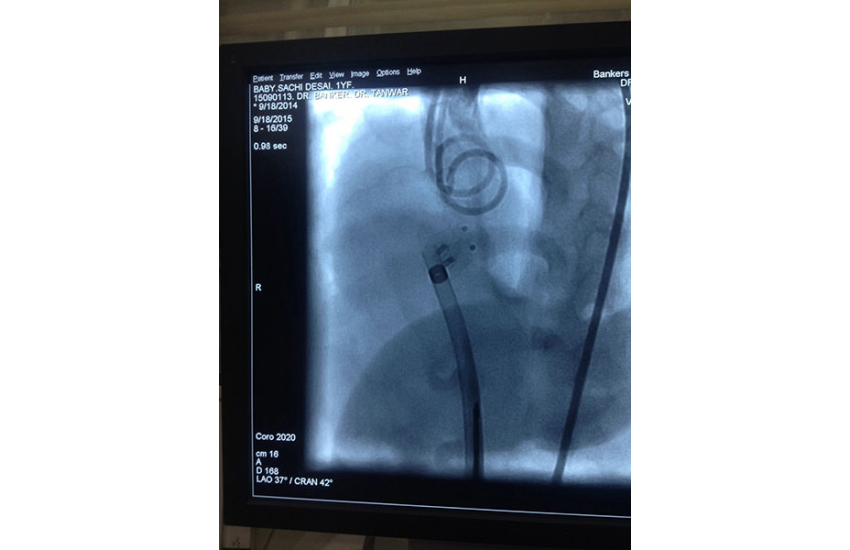

1 year girl with 7 kg weight successfully undergone Ventricular Septal Defect device closure.